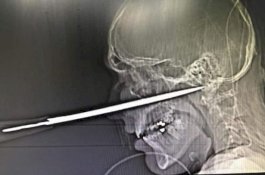

Pria Nyaris Tewas Usai Pisau Tertancap di Wajahnya, Kurang 1mm dari Kematian

News

- 15 Februari 2020 09:27